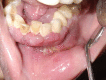

Destructive lesions in the craniofacial region especially in the jawbones, if associated with giant cells, include a spectrum of lesions that pose difficulty in diagnosis. The nature of such a lesion in the jawbones is questionable about whether it is a reactive/benign lesion or aggressive/non-aggressive. Clinical, radiological and histopathological correlation may be a reliable indicator to differentiate between the qualities of the lesion, which directly accounts for effective and individual planning of the treatment. Here we present a case of a woman in her late 20s with an unusual destructive lesion of the mandible.